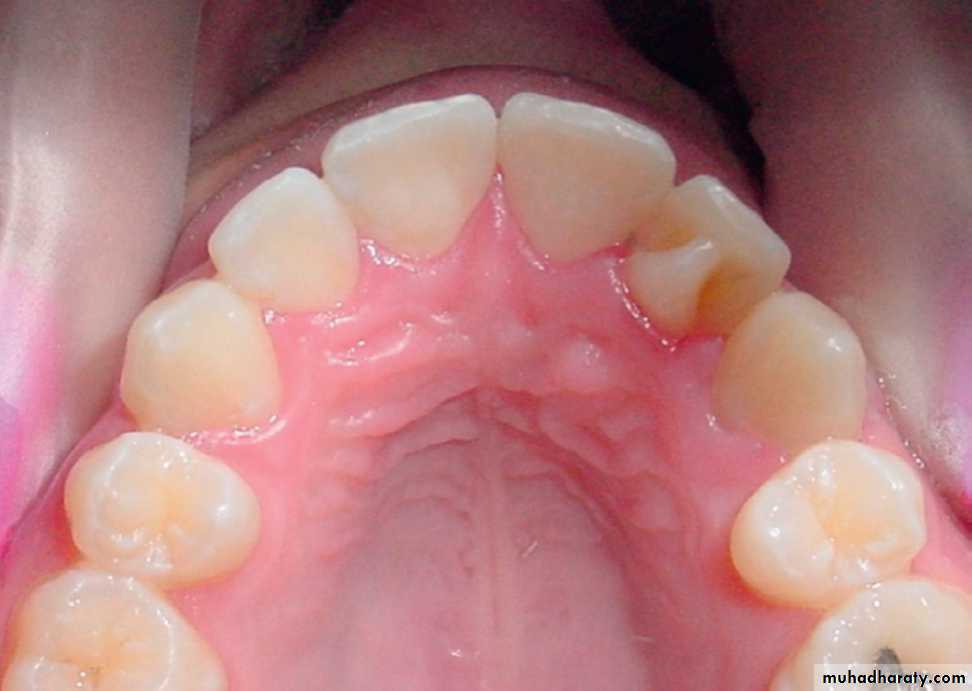

1. increase in number (Supernumerary tooth or hyperdontia)Rudimentary supernumerary, conical form.

HYPERDONTIA OR SUPERNUMERARYReasons :

• continue budding of enamel organ

• the cells become more fully differentiated and detached from the enamel organ